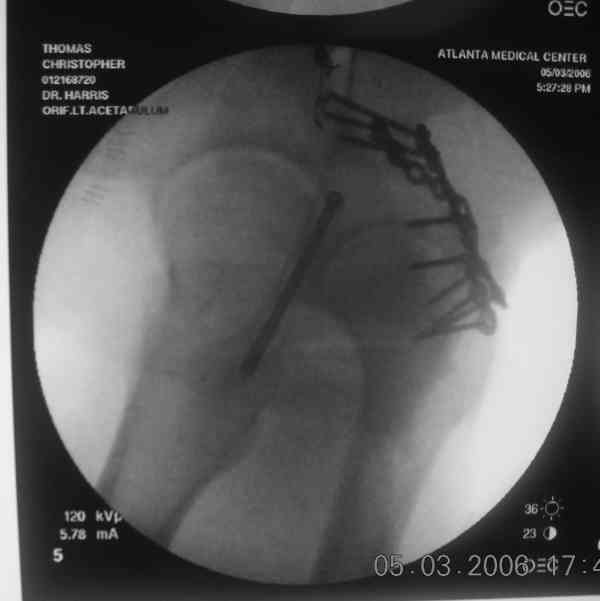

the case that I found is a 20yo male, MCC. his AP pelvis shows an interesting position of his bladder. it is pushed aside by a hematoma from SGA injury. we did a limited lateral window approach for the anterior column first, pt bumped up/supine. then closed and repositioned for KL. I could not find intra-op photos of cases when we did only a small incision for the AC screw (but they do exist!!). the lateral window is available for reduction assessment if a KL approach is being used. in the lateral position this window is available. the prone position definitely takes pressure off of the post column and facilitates reduction. in the lateral position a schantz pin in the ischial tub +/- bone hook in sciatic notch helps with PC reduction. the lateral position also gives better airway access for anesthesia. airway problems are rare, but prone position seems to be a bit more of a challenge to exchange the tube, or reintubate altogether. just something further to debate!